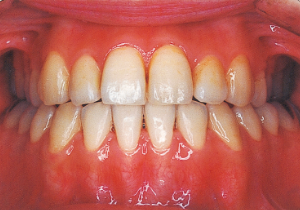

2 After Phase 2 Treatment 5-9-’92

16 5-9-’92 After Phase 2 Treatment

First Phase treatment: Treatment continued for a long period of 2 years and 5 months, from age 8 years and 6 months to age 10 years and 11 months.

Afterwards, follow-up was conducted, but based on the growth pattern, surgical intervention was determined necessary, and the patient entered a period of regular observation.

Regular Observation: 8 years from 10 years 11 months to 18 years 11 months

Second Phase Treatment:

Pre-surgical orthodontic period: 9 months

Hospitalization period: 2 weeks

Intermaxillary fixation period: Approximately 1 month (orthodontic treatment was not possible during this period).

Post-surgical orthodontic period: 10 months

Retention period: 2 years 5 months

Total Management Period: 15 years from 8 years 1 month to 23 years 1 month